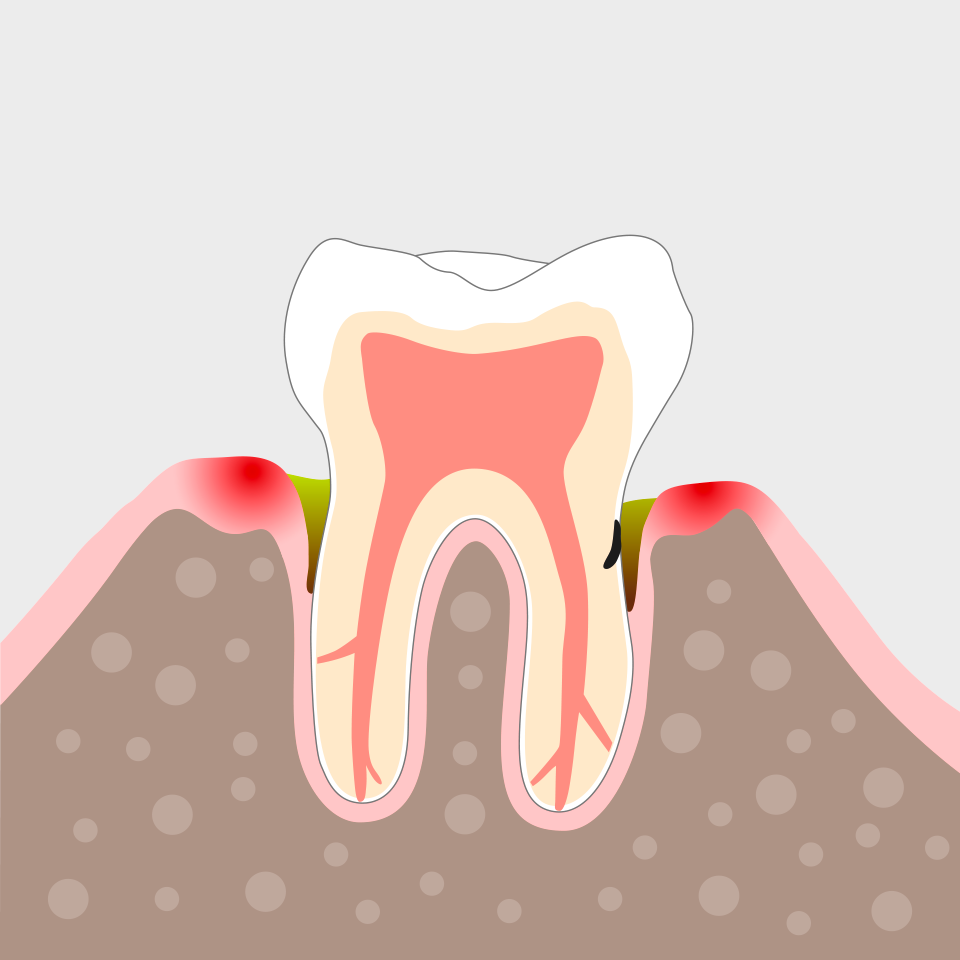

… und dann säubern wir auch die Zahnfleischtaschen.